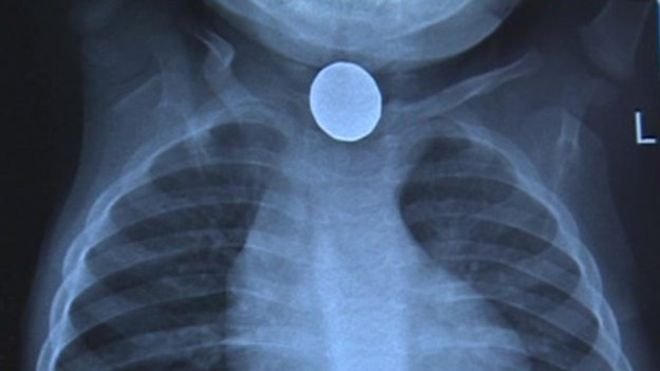

Хүүхдийн нас барсан шалтгааныг тогтоохоор цогцсыг задлан шинжилгээнд оруулахад, хүүгийн мөгөөрсөн хоолой цоорсны улмаас амь насаа алдсан болох нь тогтоогджээ. Талийгаач хүү хагас жилийн өмнө цагны зай залгисны улмаас өвдөж, улаан хоолойн мэс засалд ороод байсан ажээ.